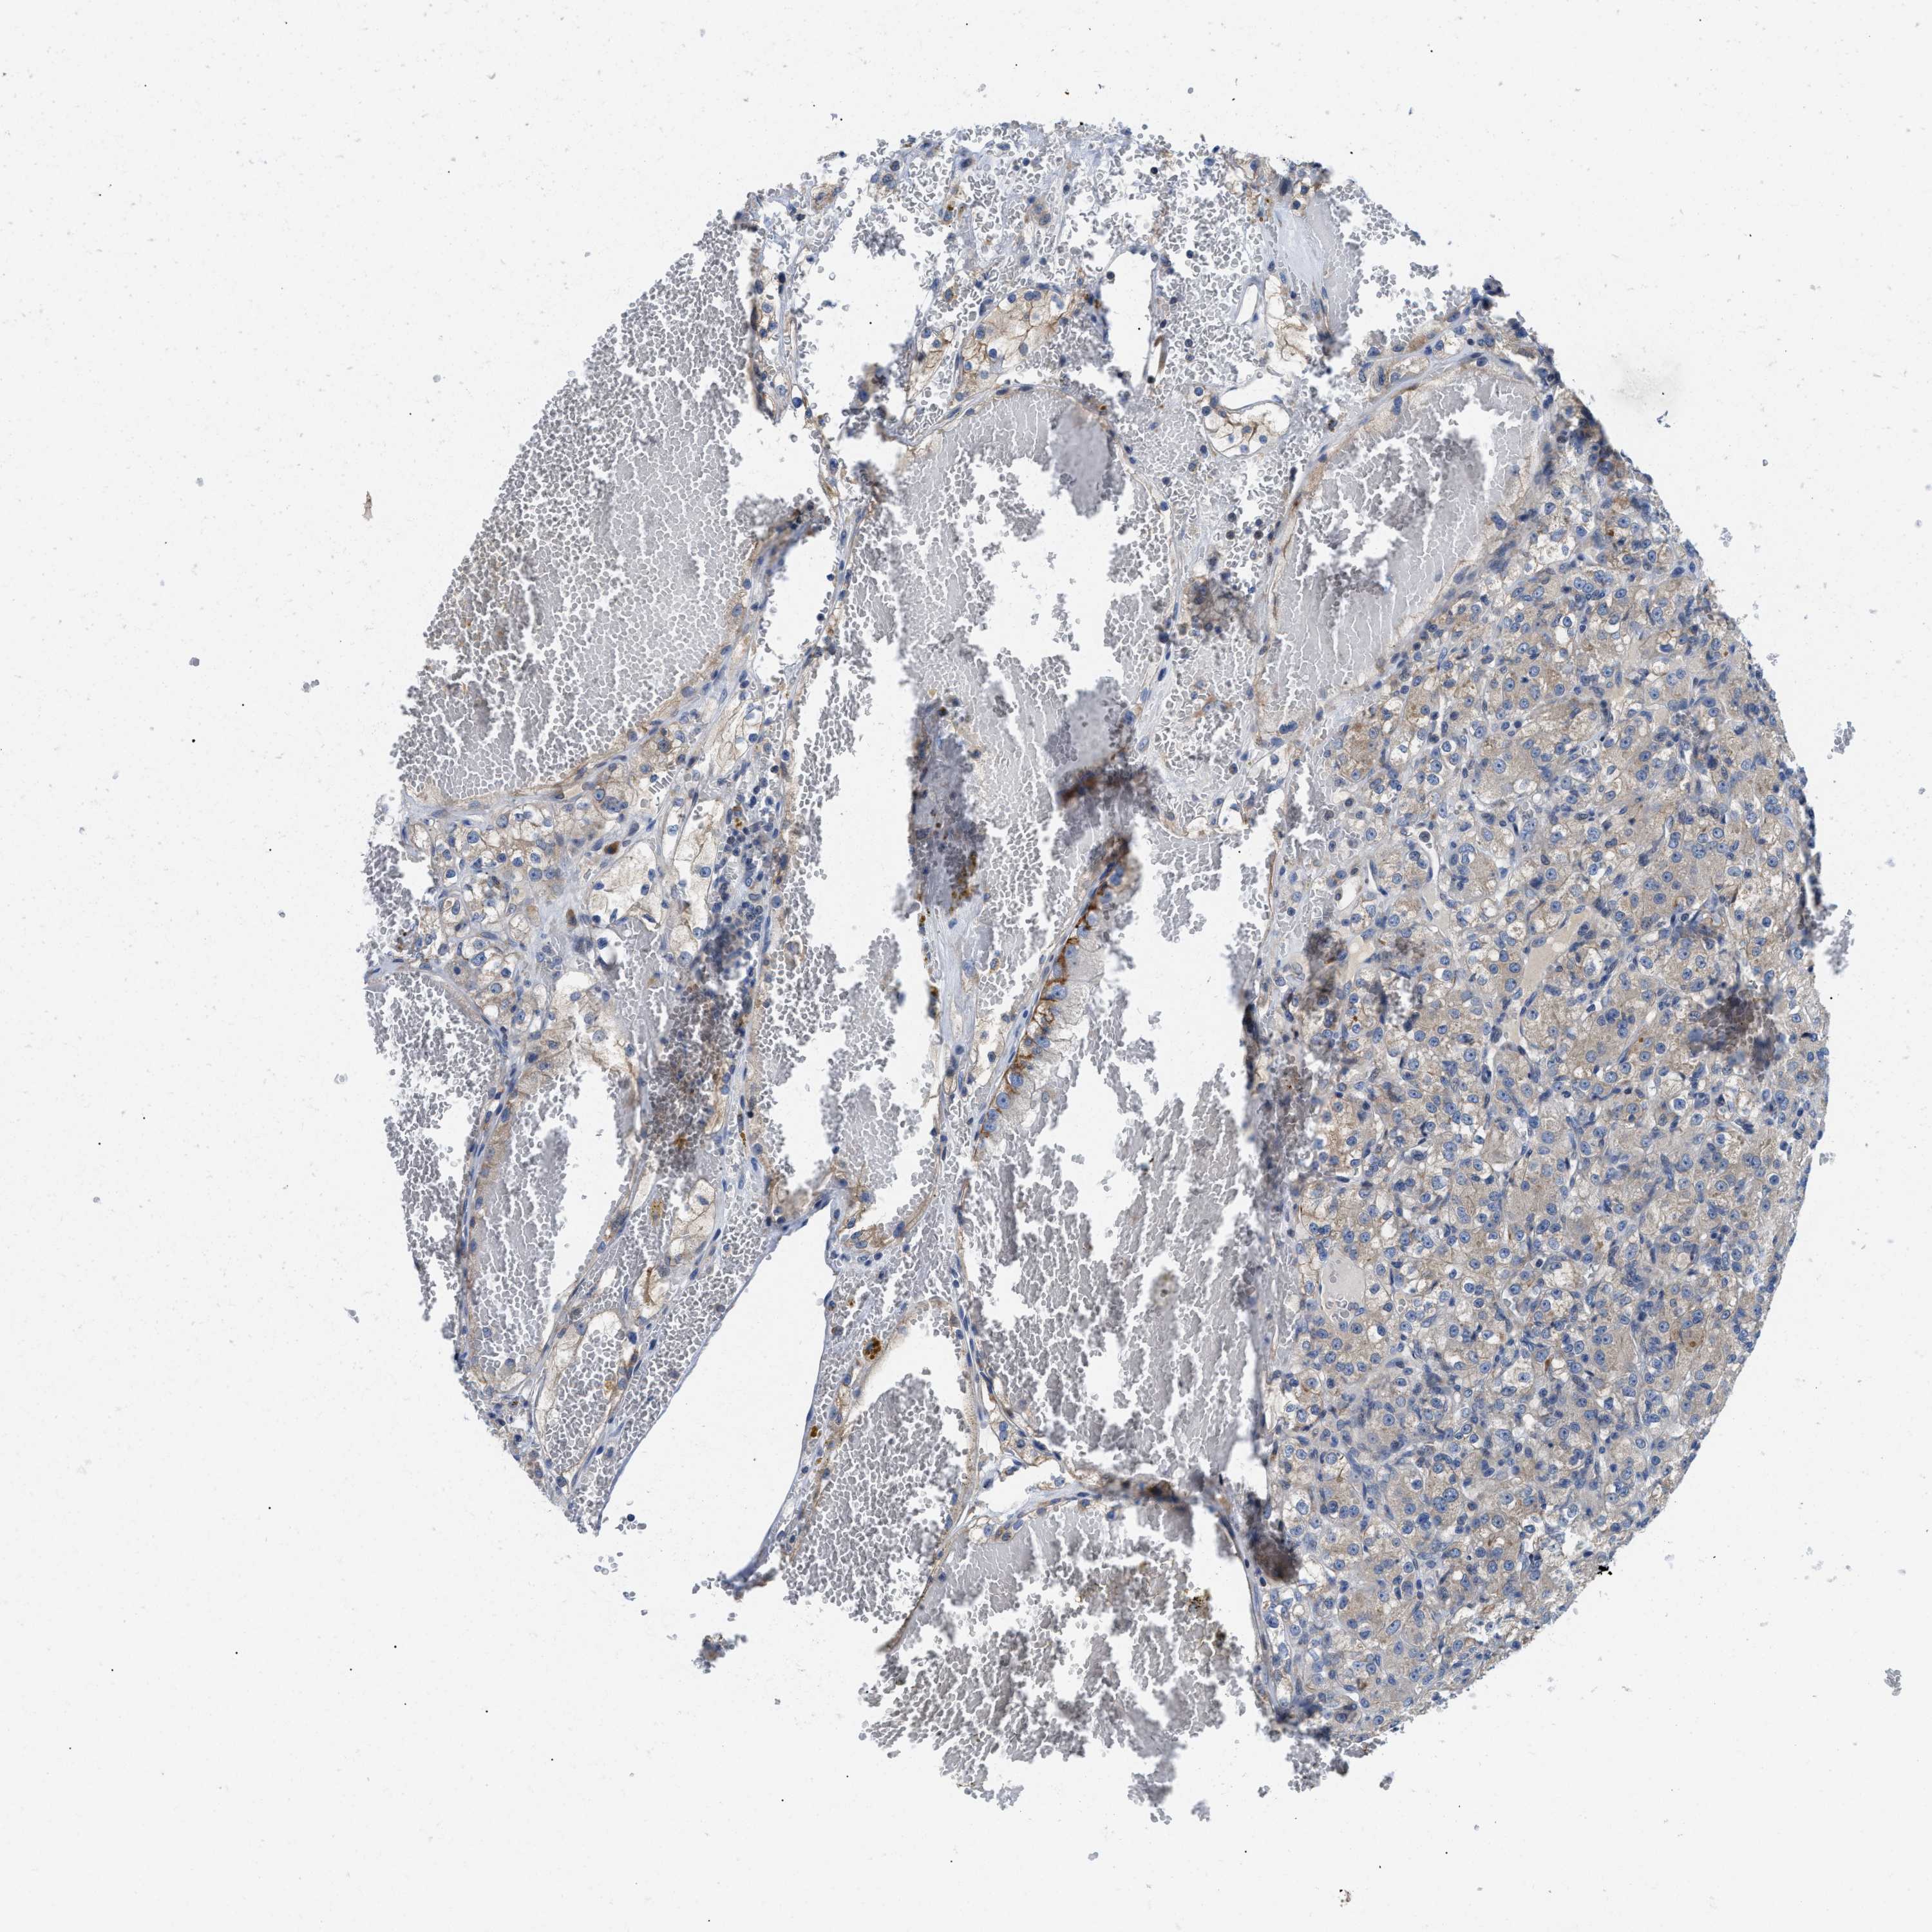

IKBKE

CANCER RENAL CANCER Show tissue menu

Renal cancer

Kidney chromophobe